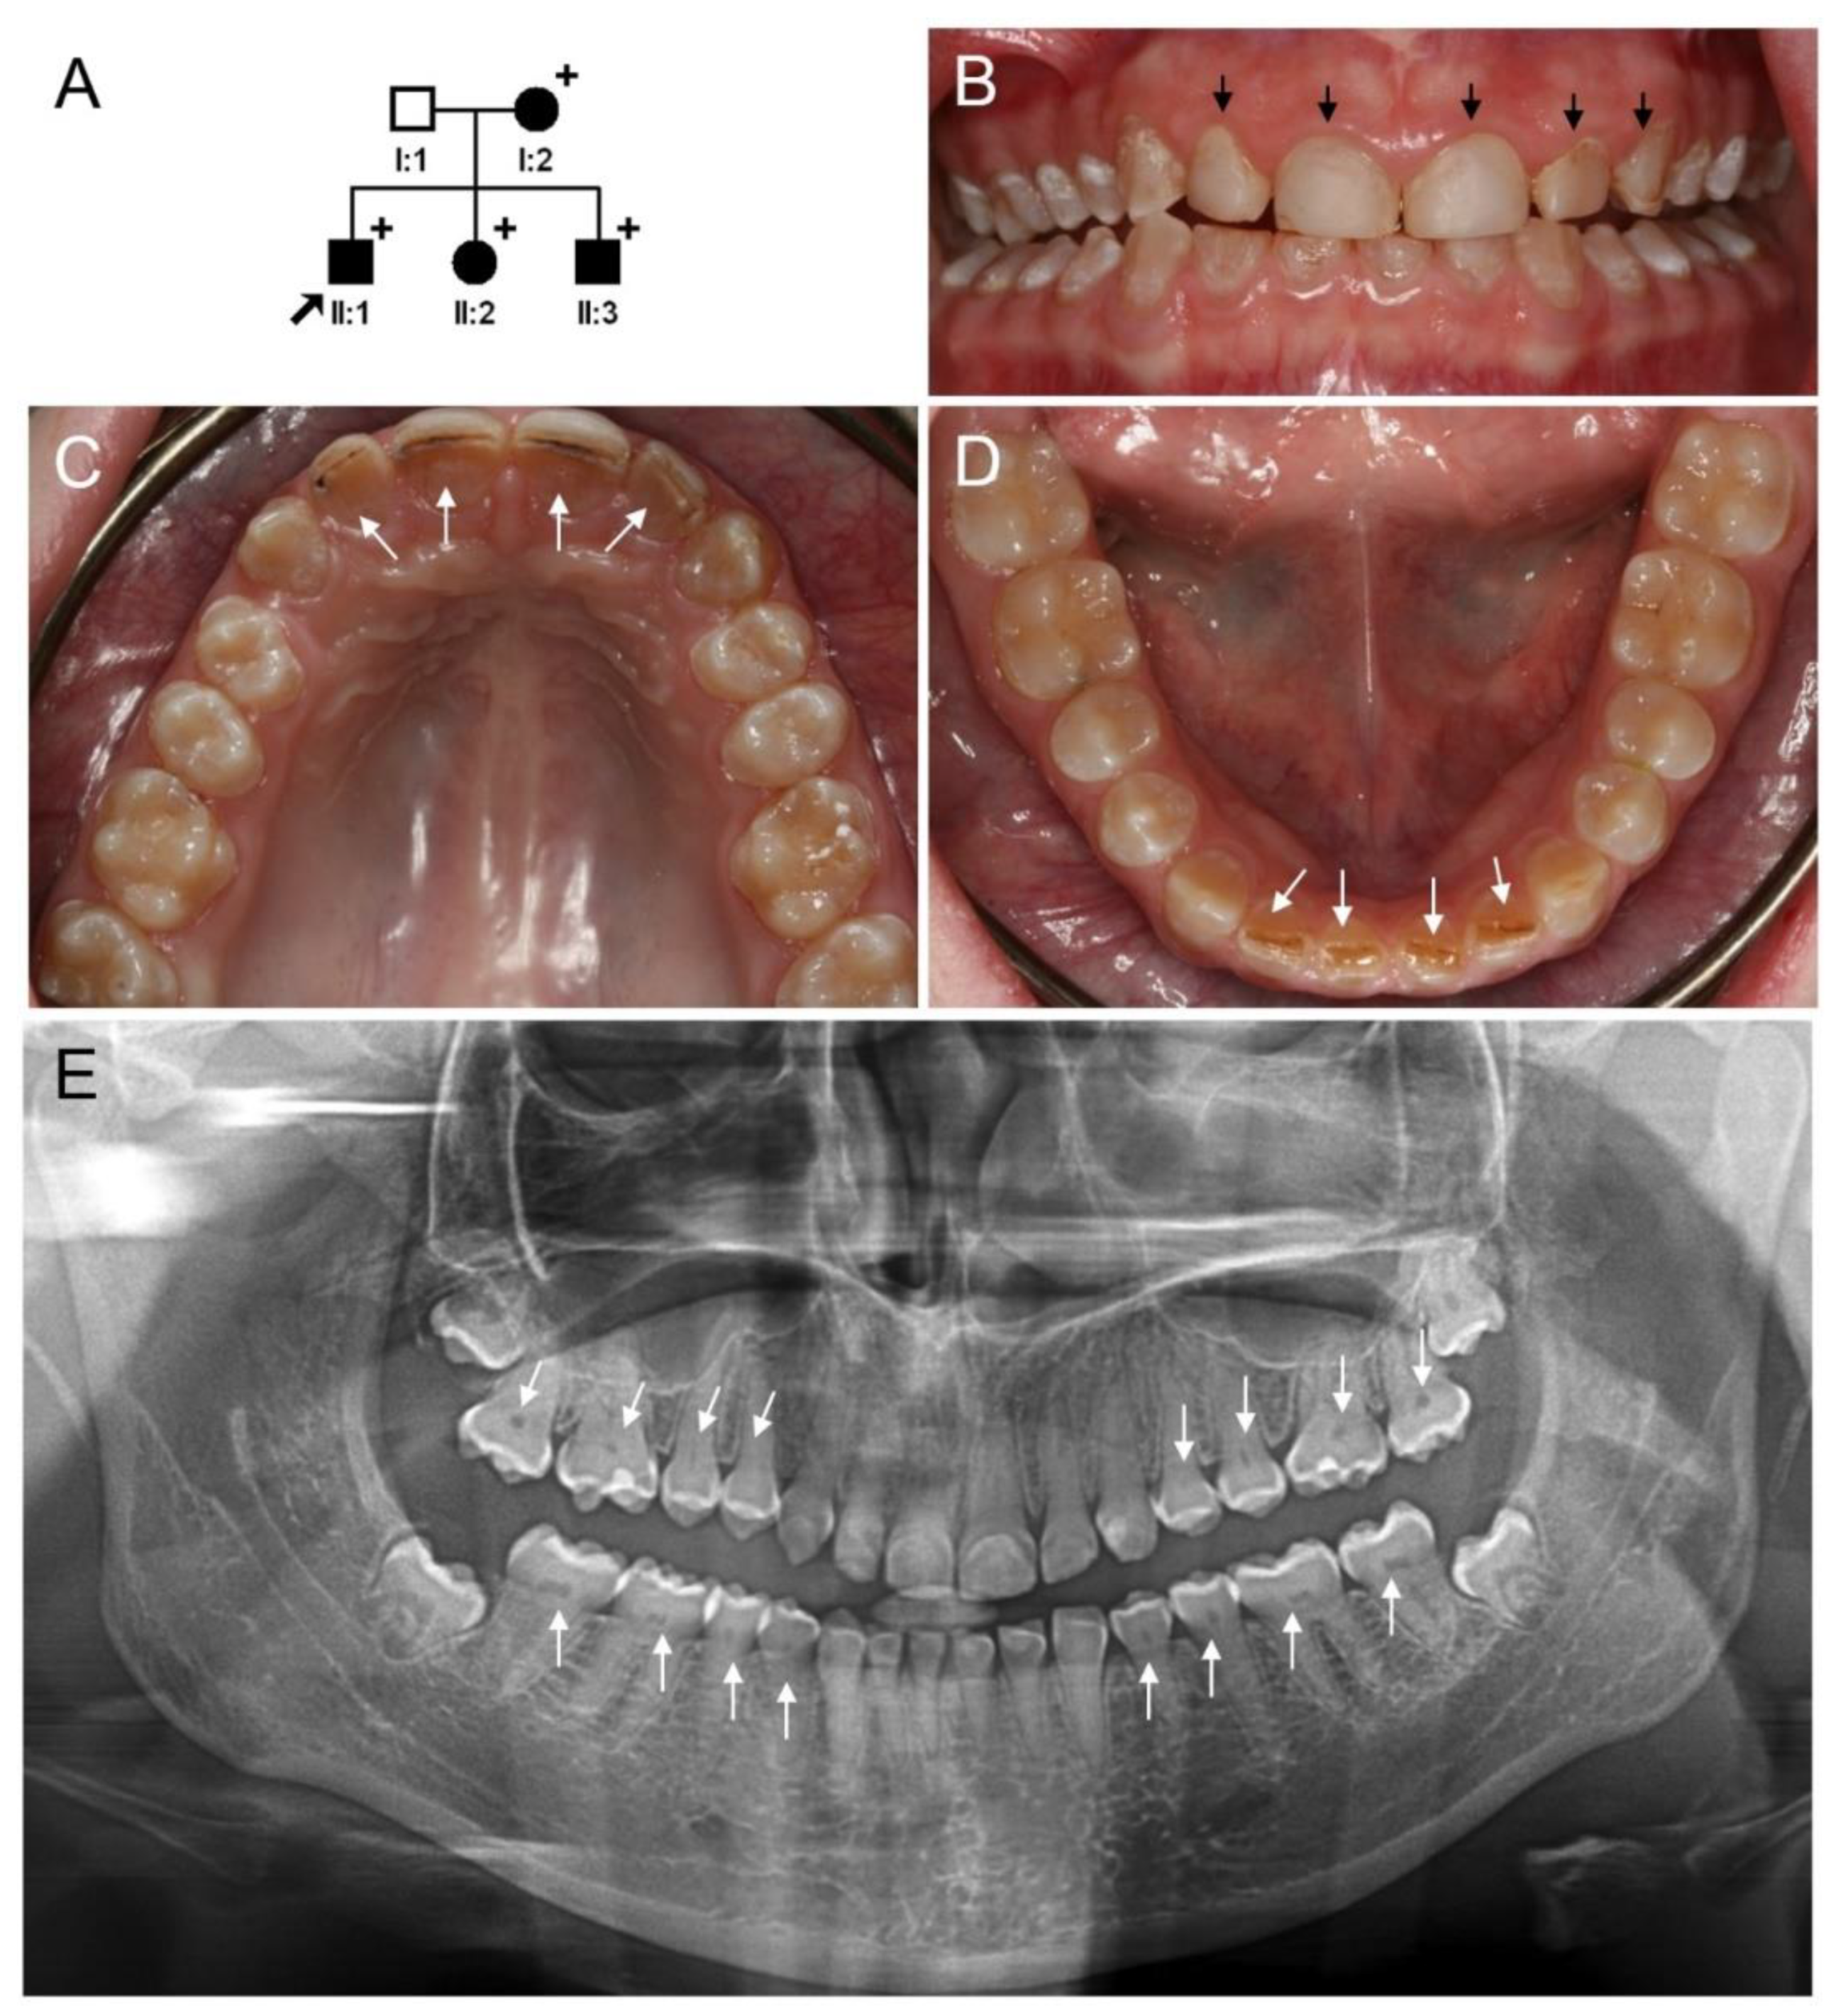

3.2. Clinical Phenotype and Diagnosis of Family 2